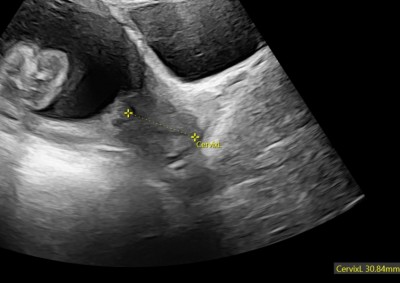

Merhaba hanımlar 19 haftalıkken rahim ağzı uzunluğum 40 mm di. Bugün 23 haftalık kontrolde doktora bakar mısınız dedim ölçtü 31 mm çıktı sıkıntı yok dedi ama panik oldum normal mi?  Çok düzgün ölçüm gelmedi bana

Gebelik haftası 23+1